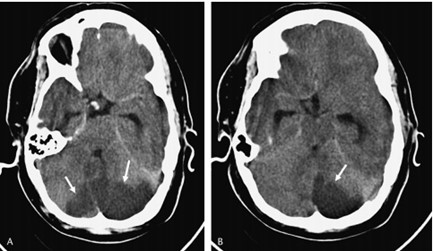

Los estudios de TC permiten evidenciar los accidentes cerebrovasculares (ACV) ocasionados por el abuso de la cocaína. Por caso, se localizó en la literatura imágenes que permiten ver el ACV isquémico agudo de la arteria cerebral media izquierda de un paciente. La TC sin contraste intravenoso visualiza la hipodensidad de la cabeza del caudado, del núcleo lenticular y de la ínsula izquierda. También se realizaron estudios de RM, que permiten observar la restricción del área isquémica en el territorio silviano(18) (ver Imagen 5).

Los consumidores habituales de cocaína suelen tener un pico de presión arterial sistólica elevada y un aumento de la frecuencia cardíaca tras el consumo, que los hace propensos a sufrir malformaciones arterovenosas. Al mismo tiempo, si esta sustancia se combina con etanol, las probabilidad de padecer una hemorragia subaracnoidea se incrementan. A propósito, se puede mencionar el caso de una paciente de 33 años de edad con síntomas de cefalea intensa y hemiparesia izquierda, en cuyo análisis de tóxicos de orina se detectó cocaína.(18)

En el caso que se viene reseñando, se realizó TC sin contraste para evidenciar eventuales daños isquémicos. En este estudio se localizó un hematoma intraparenquimatoso (ver Imagen 6). Este tipo de hematomas tiene un significativo riesgo para la persona, dado que puede avanzar hacia hemorragias con daño en la barrera hematoencefálica e incremento de la presión intracraneal, que puede ocasionar déficit neurológico e incluso la muerte.(17, 18)

En los casos de personas sin patología vascular subyacente, las hemorragias intraparenquimatosas se localizan con mayor frecuencia en los ganglios basales y el tálamo. Un caso como este se obtuvo en la literatura, correspondiente a una mujer de 23 años que sufrió una hemiplejía completa. Se le localizaron cantidades considerables de cocaína en el análisis de orina. La RM evidenció una isquemia en la rama MCA derecha con afectación de los ganglios basales(17) (ver Imagen 7).

Otro caso que conviene referir es el de una mujer de 19 años, quien acudió al servicio de guardia por dolor de cabeza agudo. Se le realizó una TC que mostró una hemorragia intraventricular con un posible componente parenquimatoso cerca de la pared del ventrículo derecho, a partir del abuso de cocaína en combinación con alcohol (ver Imagen 8). De igual modo, la angiografía evidenció una malformación arteriovenosa coroidea alimentada por la arteria coroidea lateral posterior(17) (ver Imagen 9).